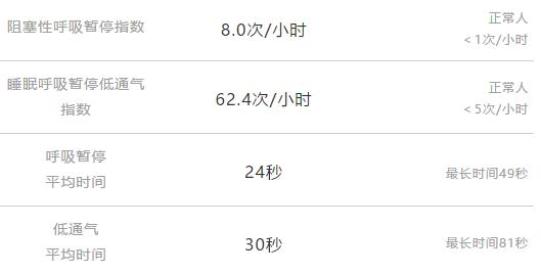

泰安一名35岁男子,在睡觉中呼吸暂停,不幸离世。他家人说,他平时身体健康,看不出任何问题。 34岁的卢医生,又高又壮。却在一次睡梦中差点断气,找到同事一检查,自己竟然每小时至少呼吸暂停40次,最高70次/小时!

34岁的卢医生,又高又壮。却在一次睡梦中差点断气,找到同事一检查,自己竟然每小时至少呼吸暂停40次,最高70次/小时! 这种病甚至连孩子都不放过。6岁的豪仔晚上睡觉呼吸暂停,最长49秒,一夜505次!他的妈妈每晚都要确认,他是不是还活着。

我们的血液会带着氧气,输送到各器官使用。人体正常的“血氧饱和度”,应该维持在95%以上。但医生监控显示,当患者睡眠呼吸暂停10秒后,血氧浓度就从95%下滑到88%,处在安全线之下!

心肌细胞等不来血氧使用,就可能导致心力衰竭。如果呼吸暂停超过3分钟,容易在睡梦中猝死。 淄博一小伙,曾因睡觉打呼噜就诊。睡眠监测发现,他每个小时呼吸暂停76次,最长能接近一分半钟。